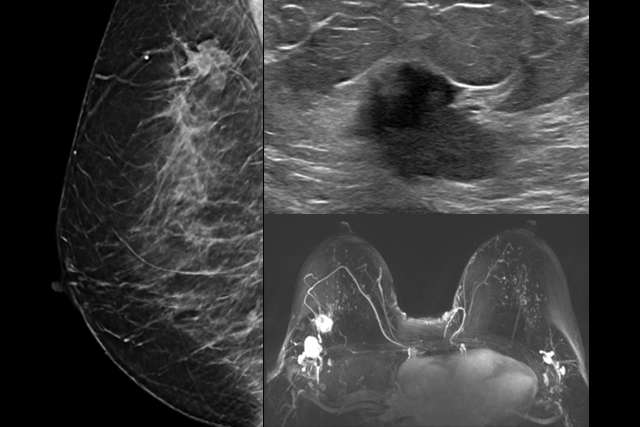

Screening Mammogram

Screening Mammogram (Screening vs. Diagnostic Mammogram)

How to obtain quality breast imaging from positioning to post-processing interpretation.